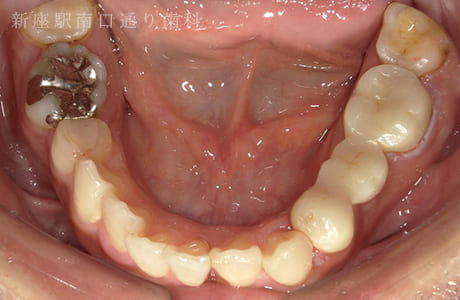

CASE.02

左上のフルジルコニアブリッジで

修復した症例

- 主訴

- 歯がないところを治したい

- 治療法

- 左上にフルジルコニアブリッジで修復

- 治療期間

- 1ヶ月半

- 費用

- ¥240,000(税込)

【リスク・副作用】

過度の咬合や衝撃で割れることがあります。治療直後は歯や歯茎に一時的な違和感や痛みが出ることがあります。